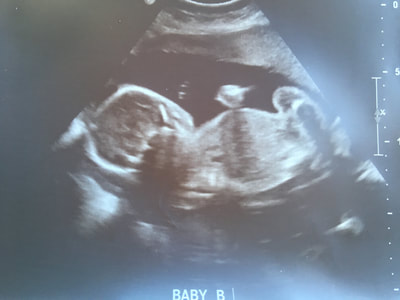

Well, large life announcement on the way…. we’re expecting TWINS! I found out just after camp that I was pregnant and got an appointment scheduled with my doctor. When I went in for that first ultrasound (what I thought was around 7 weeks) actually turned about to be 9 weeks AND there was more than one baby. Ironically the tech asked me if there were twins in my family and at first I said no forgetting about my aunts ;p So guess I got that gene… haha!